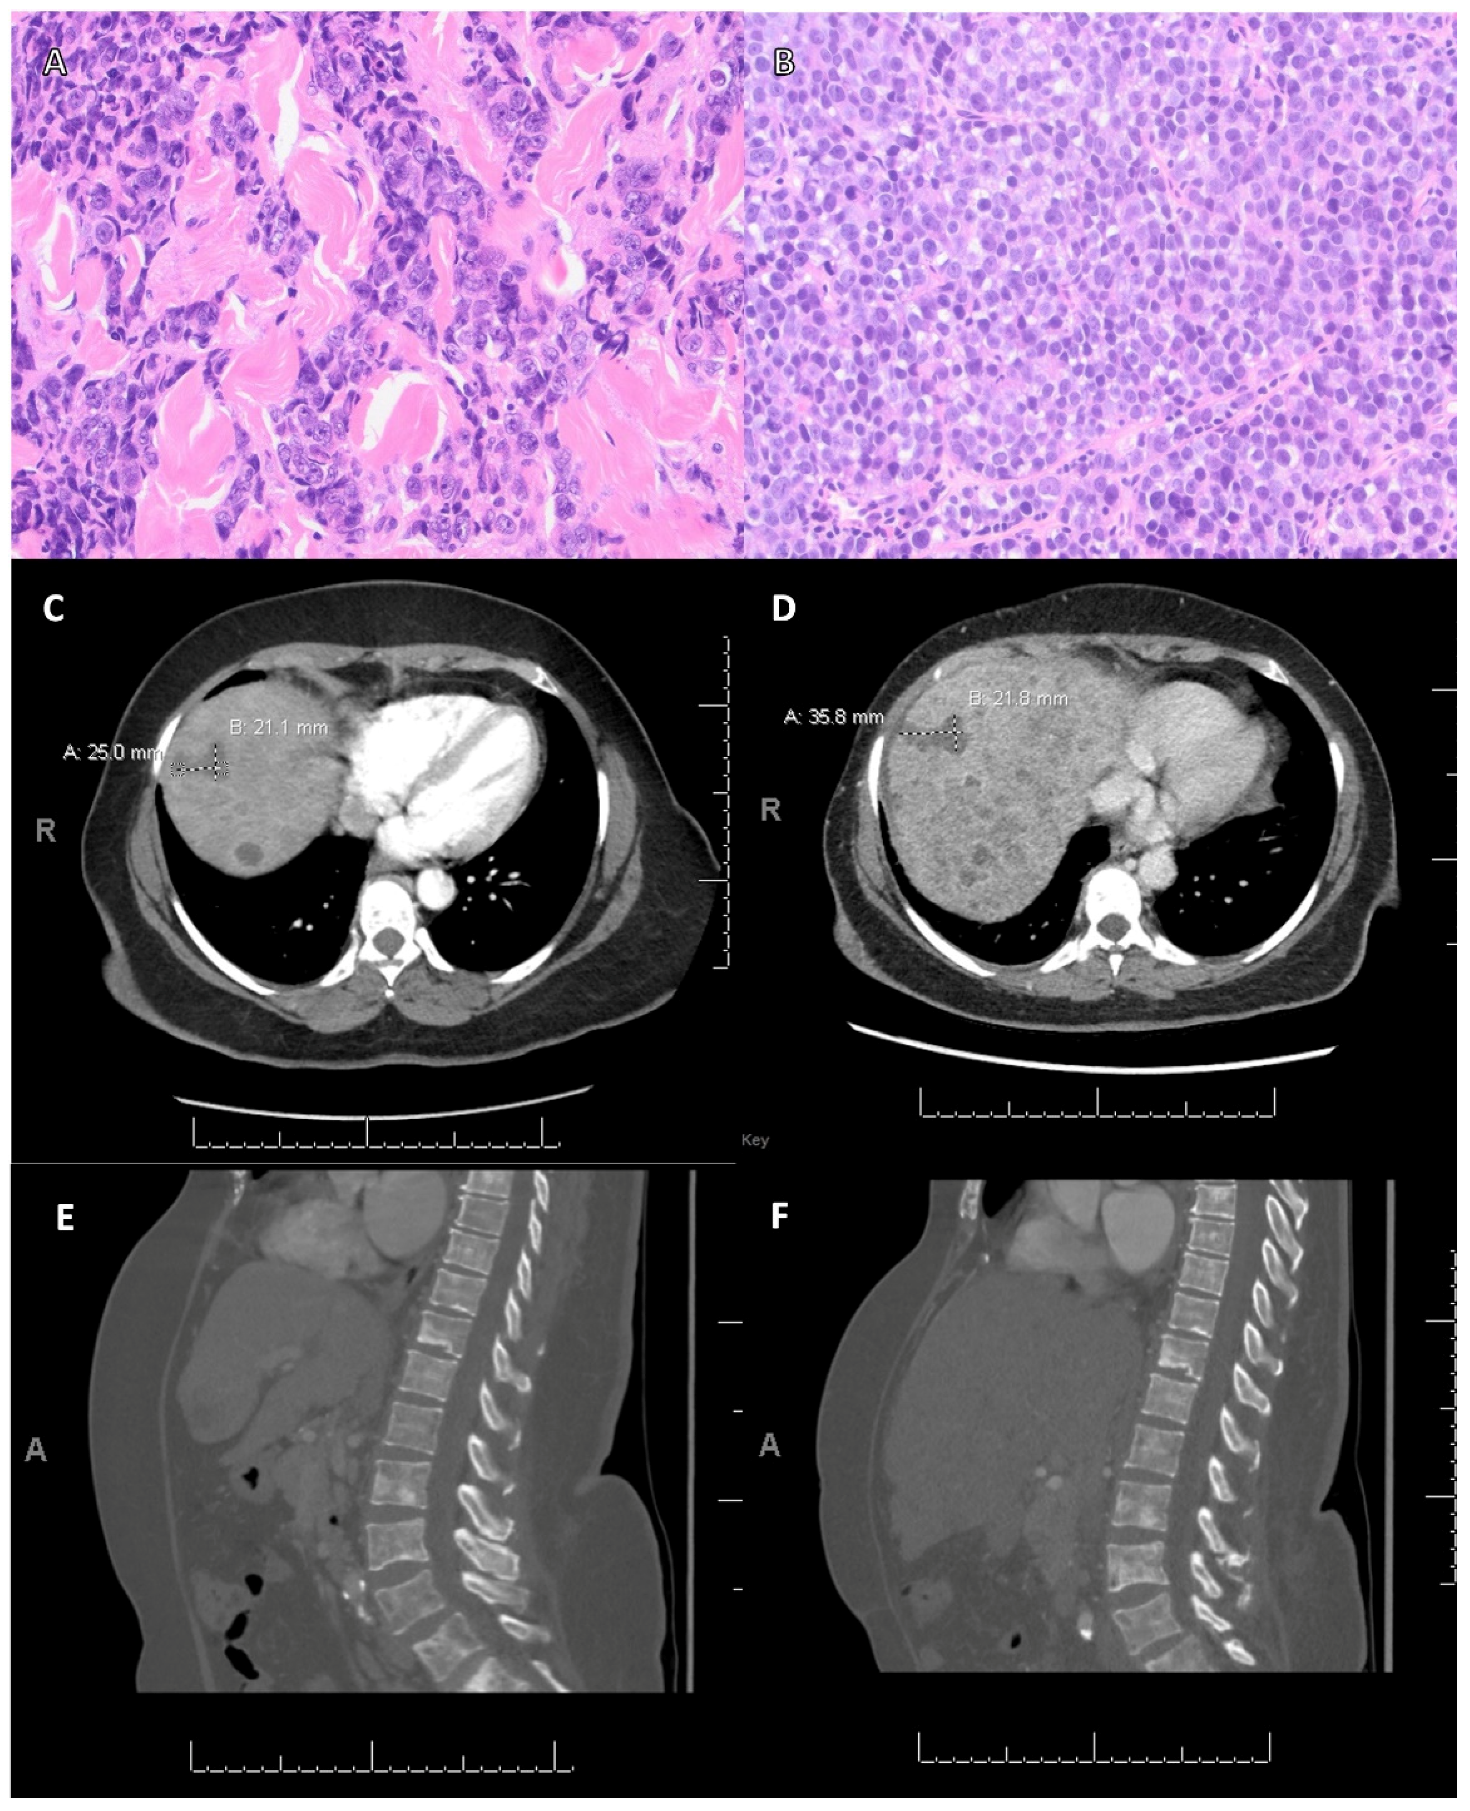

| Case | Age | Primary Tumor a | Lymph Node Status | History of Treatment | NGS g | LOH (%) | TMB (Muts/Mb) | PARPi d | Follow-Up e (Month) | Clinical Response f | ||||||||

|---|---|---|---|---|---|---|---|---|---|---|---|---|---|---|---|---|---|---|

| Diagnosis | NG | ER | PR | HER2 | Surgery b | Systemic Therapy c | Radiation | Method | HRR Gens | Non-HRR Gens | ||||||||

| 1 | 46 | IC-NST | 2 | Pos | Pos | Neg | Neg | PM | Docet Cytoxan Tamox | Yes | IVD | PALB2 p.Y1108fs*6 PALB2 p.K480fs*6 | Rad21 Amplified RARA p.M284I | N/A | 3 | O | 7 | PR |

| 2 | 59 | IC-NST | 3 | Neg | Neg | Neg | Neg | TM | Docet Cytoxan Doxor Pembro | Yes | IVD | BRCA1 p.V757fs*8 | PTEN loss MYC amplified CDKN2A/B loss EP300 truncation intron 27 FAS loss GATA6 amplified LRP1B p.R441* MCL1 amplified NUP93 p.R709T TP53 p.L257P | N/A | 5 | O | 40 | DF |

| 3 | 20 | IC-NST | 3 | Neg | Neg | Neg | Pos | TM | Doxor Cytoxan Carbo Taxol | Yes | IVD | BRCA1 p.R1751 | CTNNA1 p.E686fs*39 RB1 splice site 2063–2106+20del64 TP53 p.R175H | N/A | 1 | O | 6 | SD |

| 4 | 60 | IC-NST | 3 | Pos | Pos | Neg | Pos | TM | Doxor Carbo Tamox | Yes | IVD | BRCA1 p.C903fs*97 FANCA p.E63* | FGF12 amplified MYC amplified PIK3CA p.P104del SF3B1 p.K700E SOX2 amplified | N/A | 6 | O | 3 | PD |

| 5 | 47 | IC-NST | 3 | Neg | Neg | Neg | Pos | TM | Atezo Nab-p | Yes | IVD | BRCA1 p.K1183R VUS | AKT1 p.E17K TP53 p.C141Y NF1 p.E1334* | N/A | N/A | O | 4 | PD |

| 6 | 59 | IC-NST | 2 | Neg | Neg | Pos | Pos | TM | Docet Herce Pertu | Yes | WES | BRCA2 p.V188M VUS CHEK2 p.Y139H VUS | AKT1 p.E17K ERBB2 amplified SPEN c.1624–1635+1del13 TP53 p.R248Q | 6 | 3 | O | 1 | Discontinued |